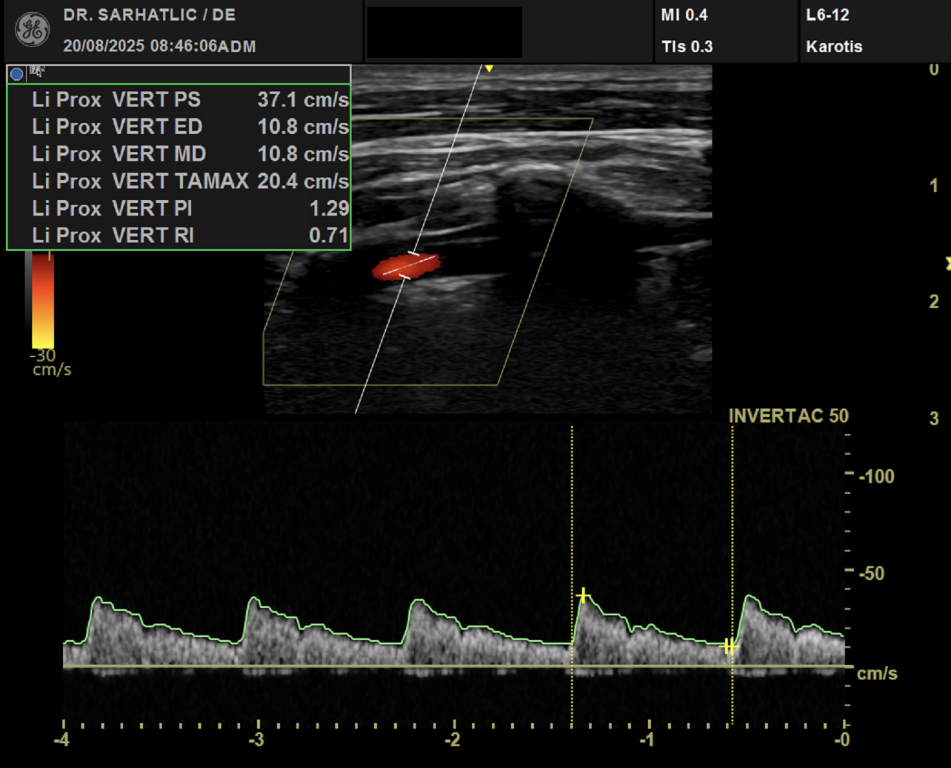

MODERNE ULTRASCHALLDIAGNOSTIK- Modernes Farbdoppler-Ultraschallgerät

- Hochauflösende Schallköpfe

- Detaillierte Organuntersuchungen

- Ultraschall der Gefäße (z. B. Halsschlagadern)